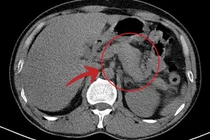

Tại Khoa Khám chữa bệnh theo yêu cầu, Bệnh viện Đa khoa Bắc Ninh số 1, êkíp phẫu thuật do ThS. BS Nguyễn Văn Hùng trực tiếp thực hiện vừa thành công trong ca phẫu thuật nội soi lấy sỏi ống mật chủ tái phát cho một bệnh nhân có tiền sử 3 lần phẫu thuật ổ bụng phức tạp.

Trước đó, bệnh nhân N.T.N (57 tuổi, trú tại phường Bắc Giang, tỉnh Bắc Ninh) từng mổ mở nhiều lần, ổ bụng dính nhiều, nguy cơ biến chứng cao. Khi sỏi ống mật chủ tái phát, người bệnh rất lo lắng vì sợ phải chịu thêm một ca mổ mở nặng nề. Sau khi thăm khám và hội chẩn, ê-kíp quyết định áp dụng phẫu thuật nội soi hiện đại – ít xâm lấn, giúp giảm đau và hồi phục nhanh.

Ca mổ kéo dài khoảng 2 giờ, các bác sĩ đã lấy sạch sỏi, đảm bảo đường mật lưu thông. Ngay sau mổ, bệnh nhân tỉnh táo, vận động nhẹ nhàng và ăn uống trở lại sau 6 giờ. Sau 5 ngày, người bệnh hồi phục tốt và được xuất viện trong sự hài lòng của gia đình.